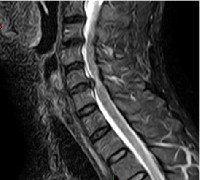

compression médullaire par hernie discale

Hernie cervicale compressive sur la moelle épinière

coupe sagittale IRM

L’imagerie par résonance magnétique (IRM) : elle permet de donner des informations supplémentaires à celles du scanner, en montrant mieux les tissus mous environnants et en permettant de donner une information sur la qualité des tissus, elle montre par contre moins bien les structures osseuses. Elle détecte particulièrement bien les lésions de la moelle épinière (myélopathie cervicale) en cas de rétrécissement du canal lié à l’arthrose ou à une très grosse hernie.